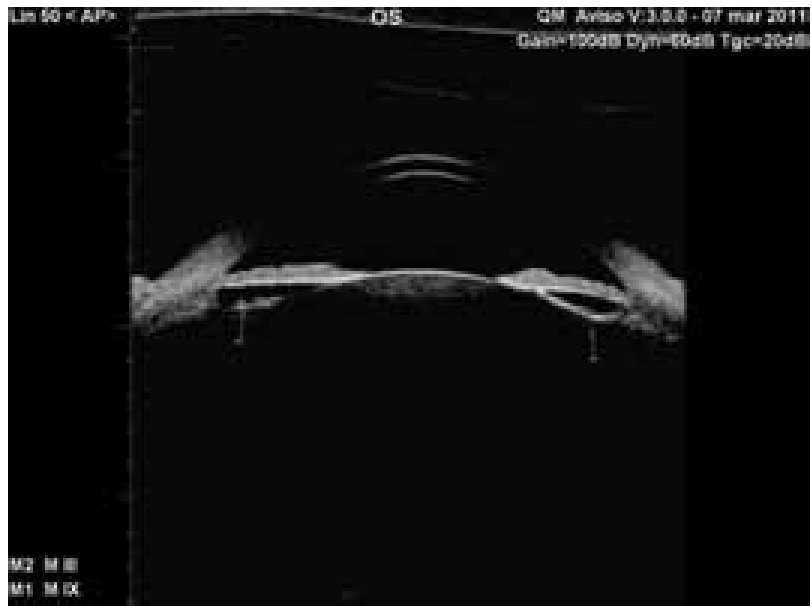

Best corrected visual acuity in the left eye was counting fingers at 1 meter. Intraocular pressure (IOP) was recorded at 63 mmHg by Goldmann applanation. On slit lamp examination, we noted conjunctival hyperemia with ciliary injection, clear cornea and shall owing of the anterior chamber with a mild dilated pupil. A pigmented mass was noted through the pupil behind the iris at the 9-o'clock (Figure 1). The optic nerve cup-to-disc ratio was 0.4 with healthy appearing neuroretinal rim. Ultrasound biomicroscopy (UBM) imaging of the left eye revealed iris thickening associated with a cystic lesion extending 360° on the posterior surface of the iris (Figure 2). The anterior chamber depth was 2.89 mm with a completely closed angle for 360 degrees. These findings suggested angle-closure glaucoma secondary to a complete ring cyst of the iris pigment epithelium. The right eye exam was completely normal.

Figure 2. UBM before treatment.